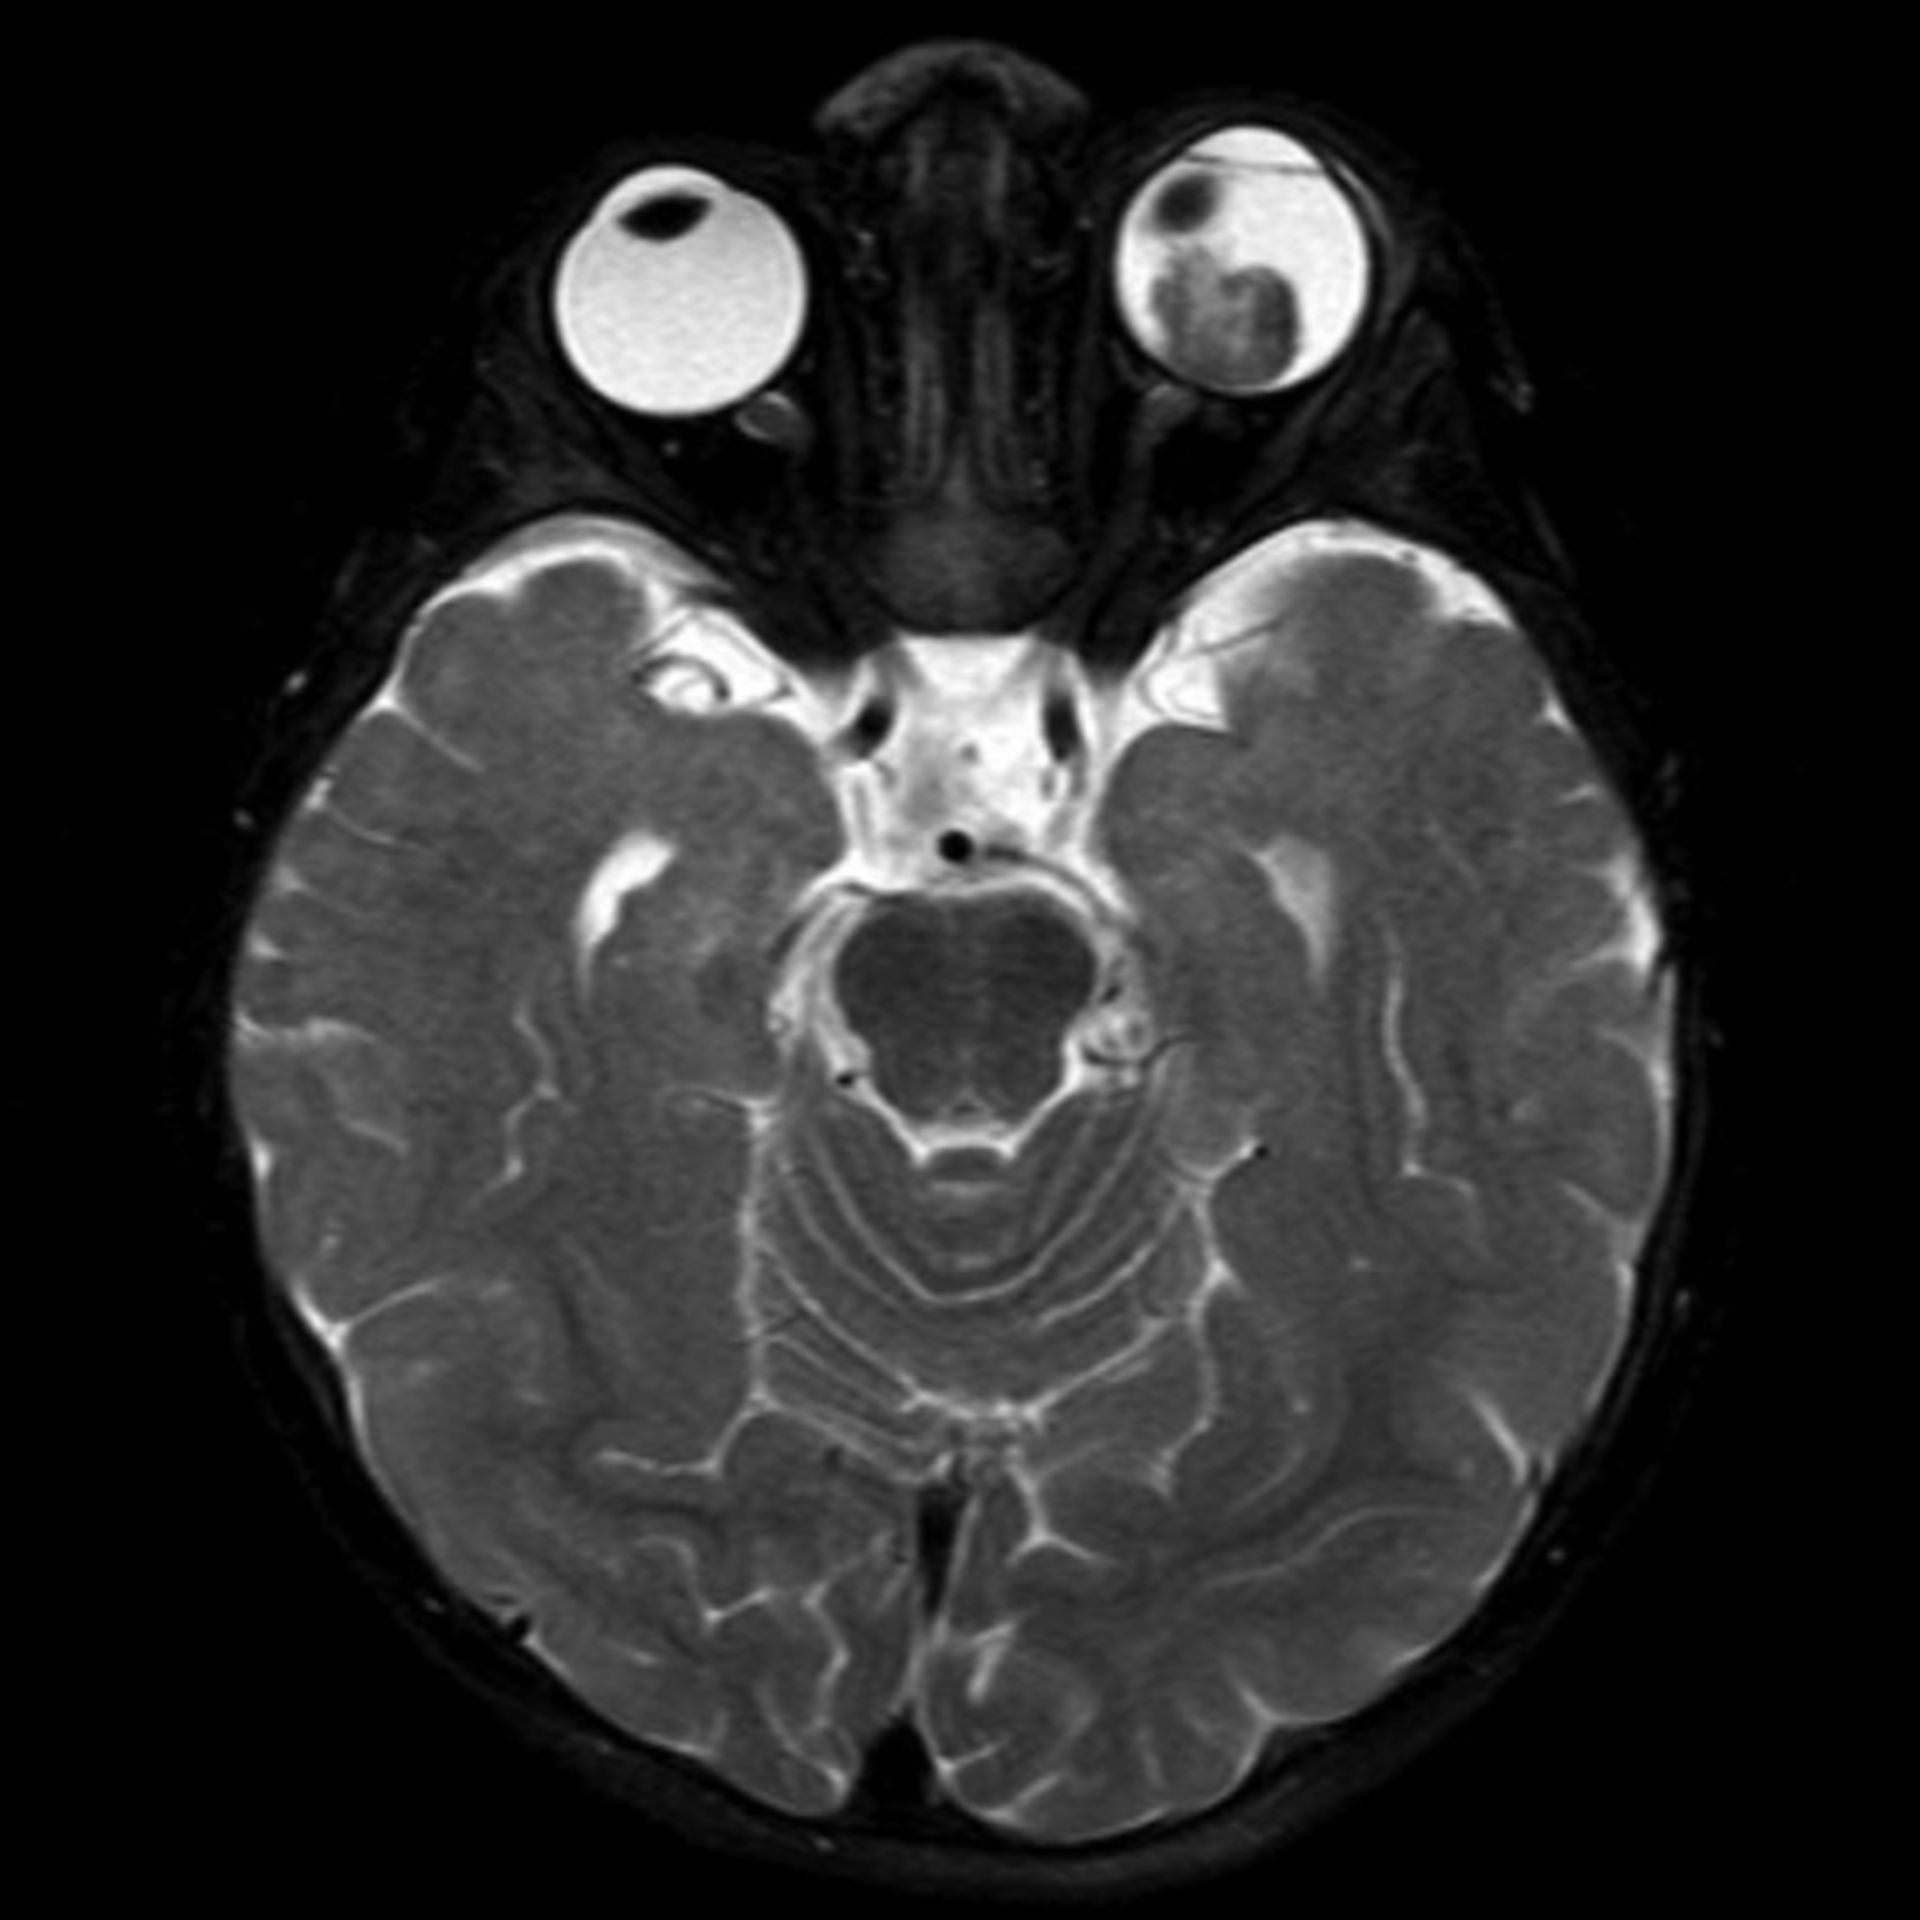

(16/26) MRT Schädel in Transversalebene, T₁‐gewichtet, FFE – DocCheck MRT Knie – DocCheck

(11/26) MRT Schädel in Transversalebene, T₁‐gewichtet, FFE – DocCheck MS Herd MRT (1) – DocCheck

Retinoblastom (MRT/T2) – DocCheck MRT: Posterior-Hirninfarkt – DocCheck

Mrt : Kuala Lumpur’s New MRT Map Alignment. ~ .: Property … / Support more model(qualcomm and … Retinoblastom (MRT/T2) – DocCheck